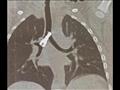

وقال الدكتور حسام العربي مدير مستشفى القلب في جامعة أسيوط، إنه جرى استقبال طفل يعاني من أعراض التهاب رئوي منذ شهر، وبعد توقيع الكشف الطبي عليه وإجراء الفحص والأشعة تبين وجود جسم معدني كبير في أسفل القصبة الهوائية وبداية الشعبة الهوائية اليمني، متابعًا "على الفور جرى إبلاغ فريق قسم جراحة القلب والصدر باتخاذ الإجراء الطبي اللازم".

وأشار الدكتور أحمد غنيم رئيس قسم جراحة القلب والصدر، إلى أنه فور تلقي القسم بيانًا بحالة الطفل المريض، جرت مناظرة الطفل بواسطة الأطباء عمرو ممدوح وأحمد سمير، والتأكد من وجود جسم معدني، وفقًا لما قاله والد الطفل إنه كان يلهو في الأرض ثم ظهرت عليه أعراض الكحة وضيق التنفس.

وأكد "غنيم" إجراء المنظار على الشعب الهوائية للطفل، واستخراج جسم معدني كبير من أسفل القصبة الهوائية؛ مشيرًا إلى خروج الطفل بصحة جيدة بعد التأكد من استقرار حالته الصحية.